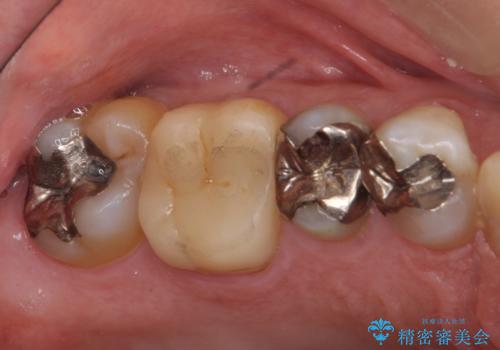

銀歯の下が虫歯 セラミックインレーに

- 銀歯の下が虫歯になっていたため、虫歯を取り、セラミックインレーで修復しました。

見るだけでは、わかりにくいのでしっかりレントゲンを診てもらえるような定期検診が大事です。